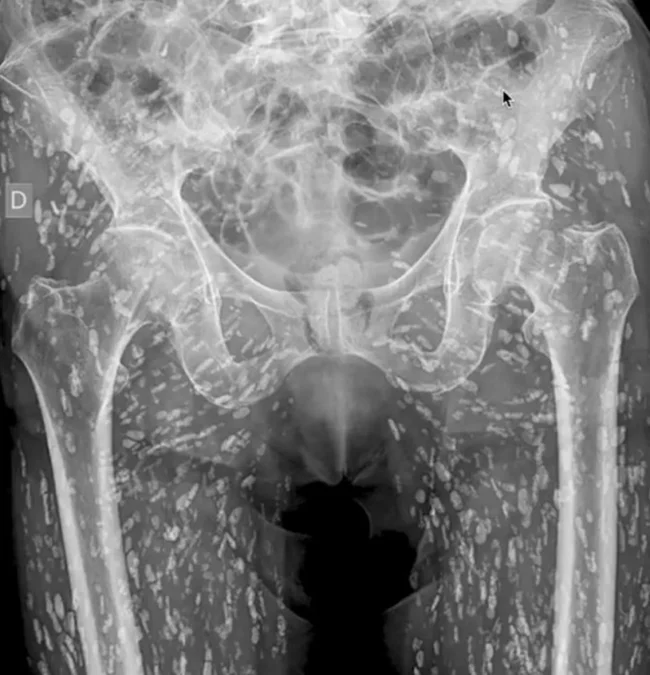

Рентген показал, что мужчина заражён сотнями яиц свиного цепня. И всему виной банальная ошибка при приготовлении пищи. Пациент обратился к врачу, когда упал и почувствовал боль в бедре.

Американский врач Сэм Гали поделился историей мужчины и отметил, что это «один из самых необычных рентгеновских снимков, которые он когда-либо видел».

Он пояснил: «Это заболевание известно как цистицеркоз. По сути, это цисты Taenia solium — также известного как свиной цепень».

«Цисты могут распространяться по всему телу человека. У этого пациента ими поражены мышцы и мягкие ткани бёдер и ног», — добавил Гали.

В данном случае паразиты не представляли угрозы для жизни. Их обнаружили, когда у пациента был выявлен перелом бедра.